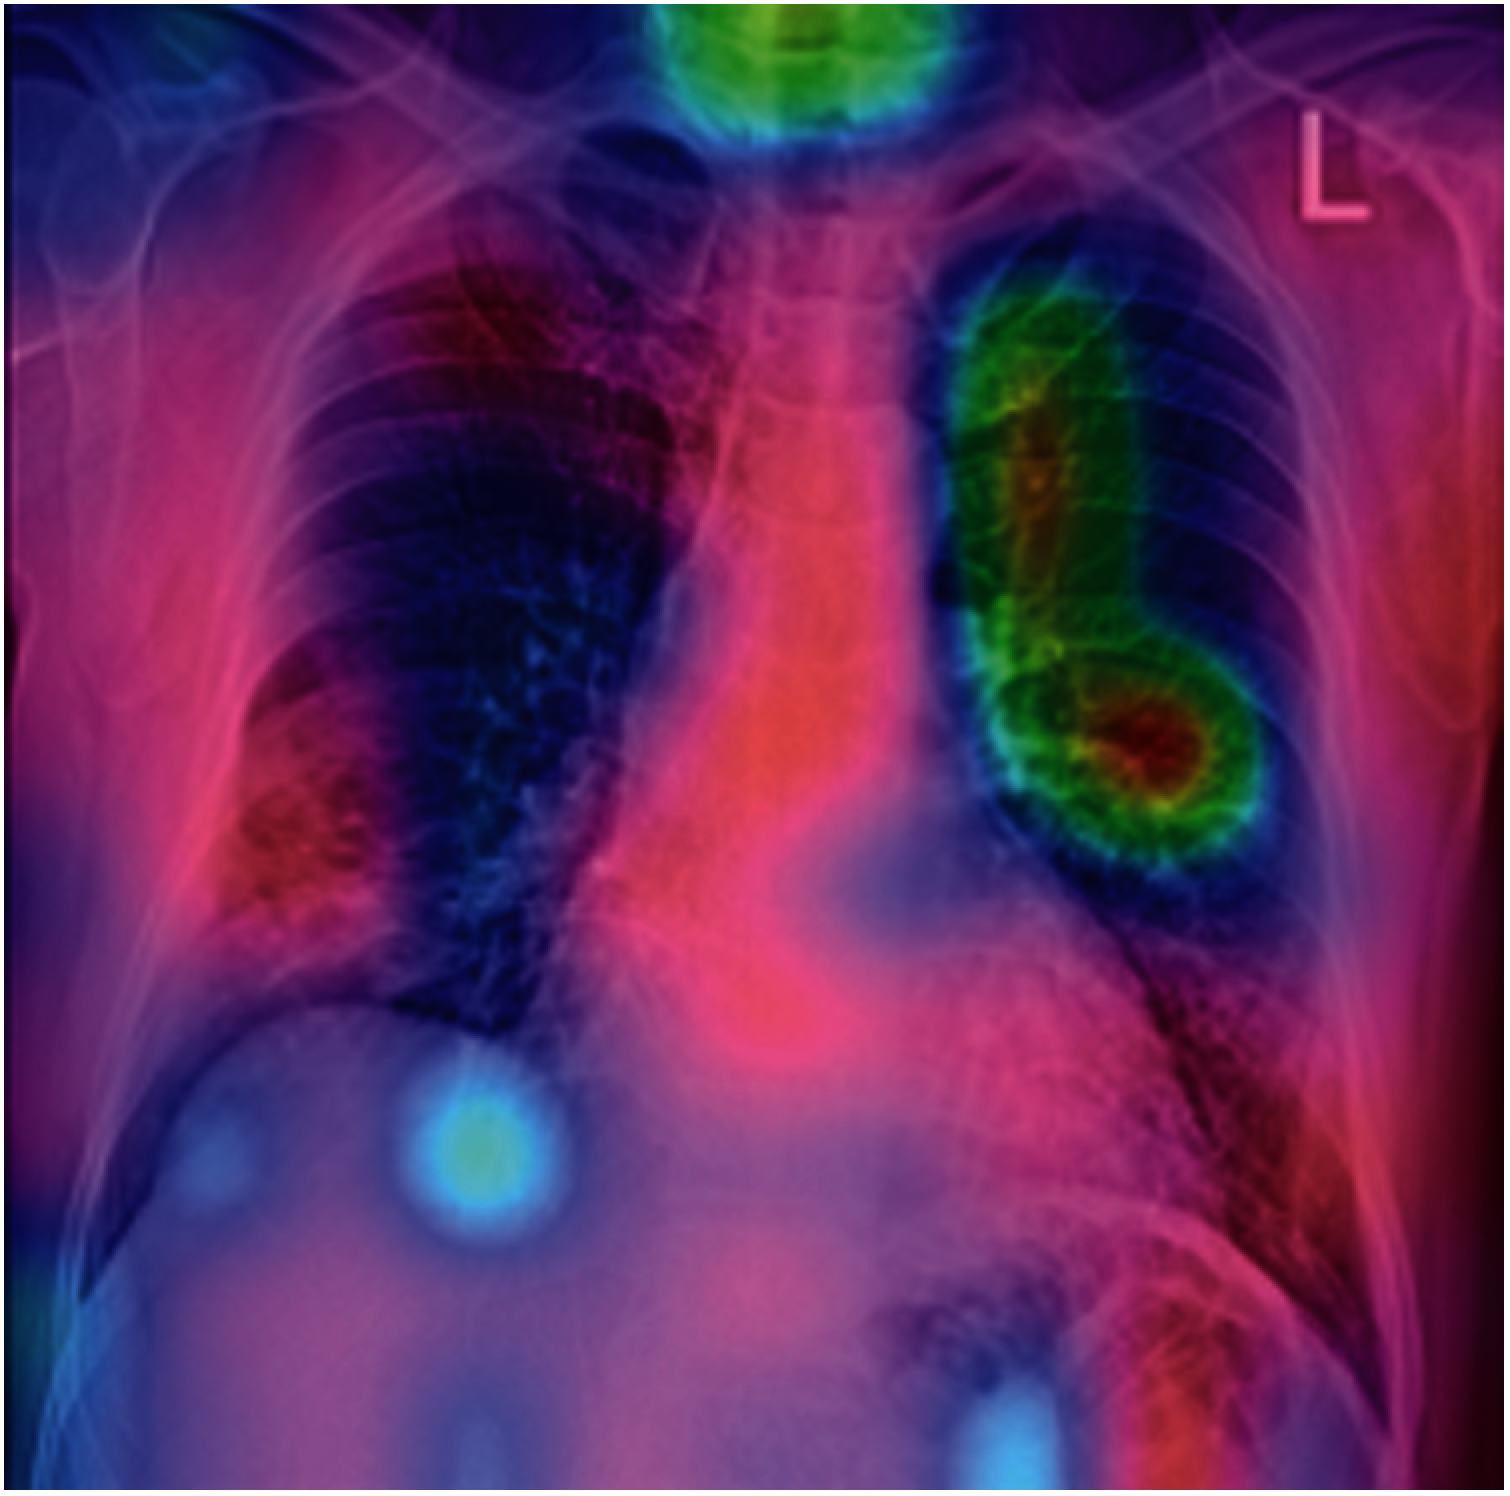

Fig. 14 shows the comparison of sensitivity, specificity and F1 score of existing and proposed techniques. The proposed system has achieved better results than the other existing techniques. The proposed Light RES-ASPP-Unet indicates the affected area with ROI process correctly at the end. ROI with ACM give a clear view on the output and has proved the predicted results as accurate. Various regions are highlighted in Covid-19 and normal cases. This proves that the proposed network classifications are very useful for medical officers and provide sensitive second opinion to the radiology teams. This helps to understand the deep neural network models and working principal.